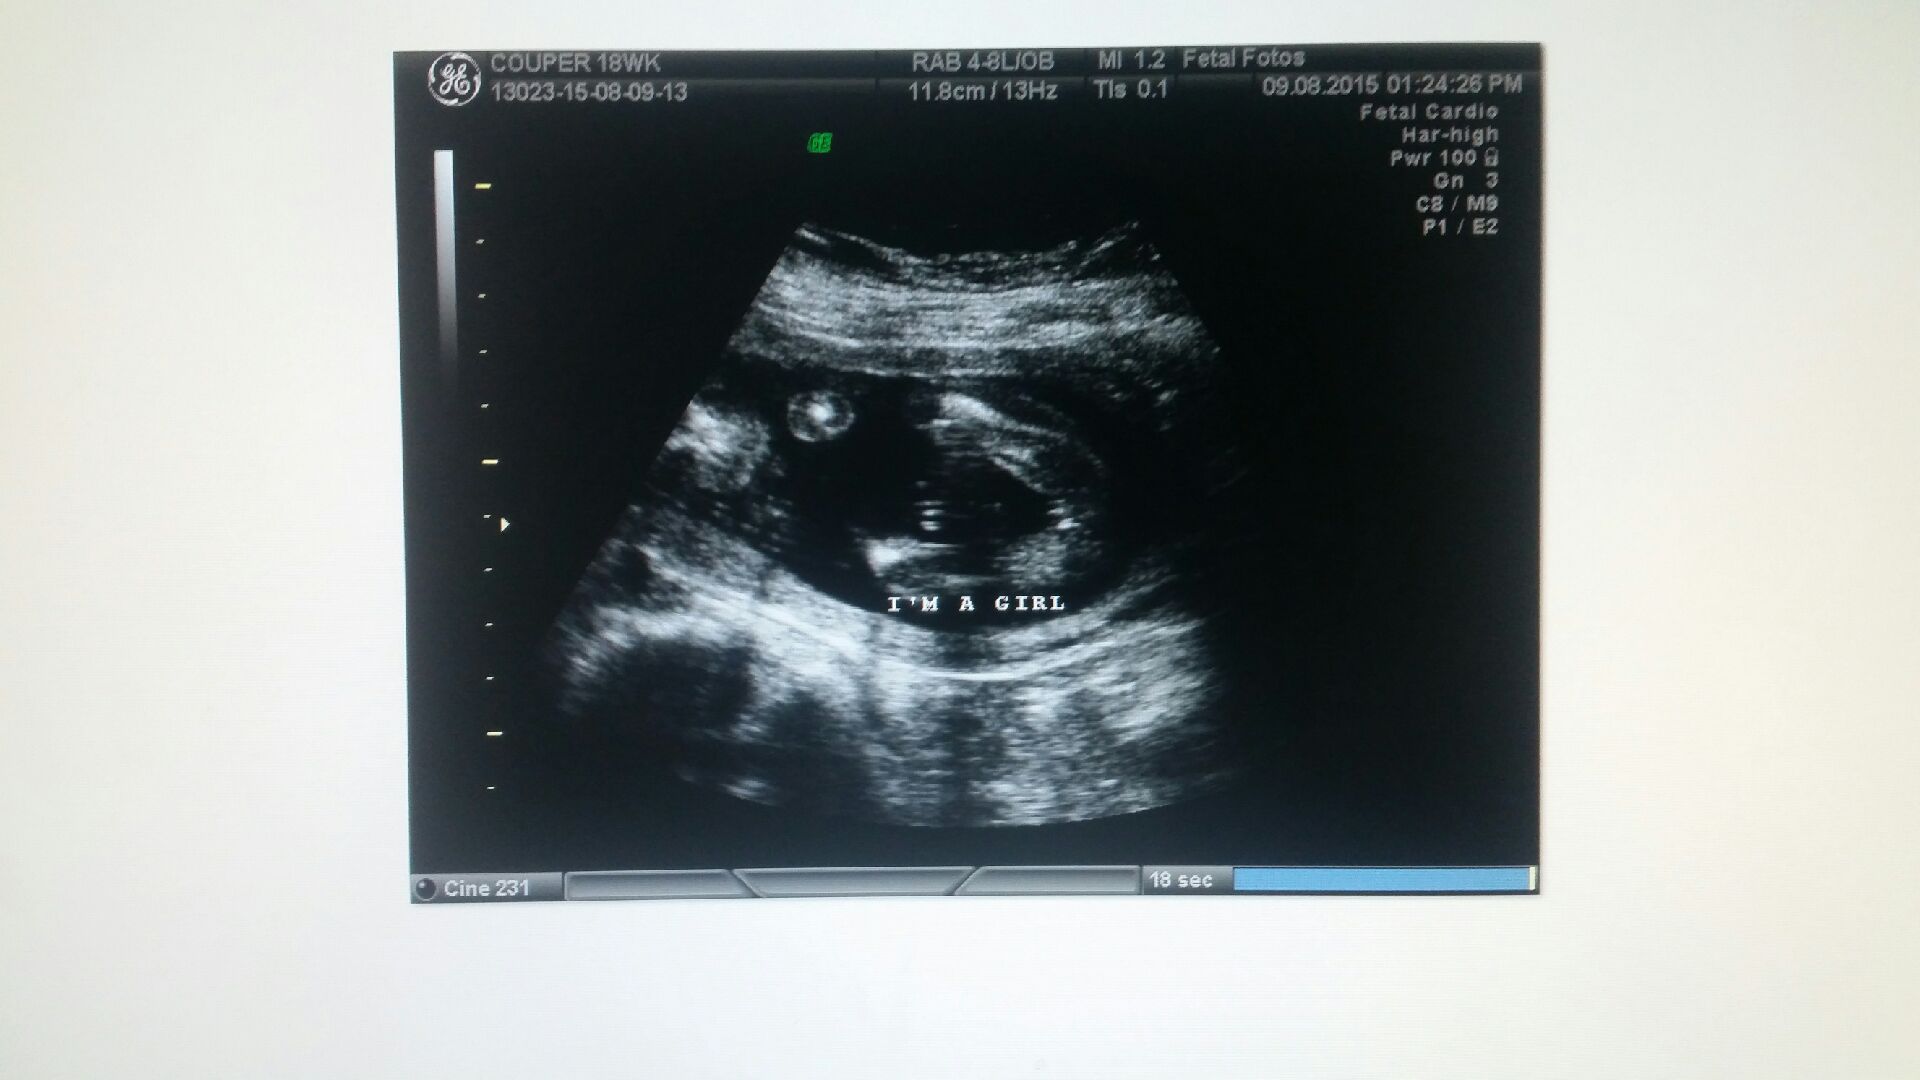

Hi ladies, first time ive had the guts to post here. 12 week scan i was told i was having my 3rd boy. Scan i had last weekend says girl. I need your expertise to let me know what you think :) Attachment 26642

Looks like a girl to me. I'd believe this over a 12 week guess any day. Enjoy your girl :)

Thanks covered in blue. Im still in shock. I never thought i would hear the words girl in my entire life. After losing a bub in jan in the 2nd trimester because it was a molar pregnancy im absolutely in heaven right now

Girl :HH::HH::HH:

Girl!! Congratulations!

Looks girly to me!